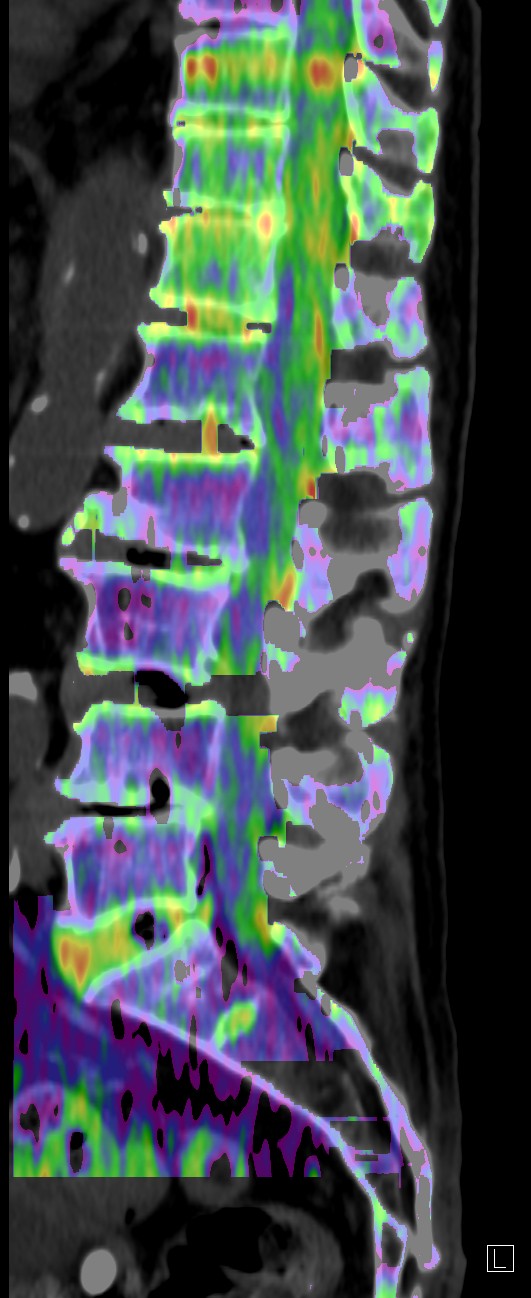

整形領域

MR禁忌や体動のある患者への対応

DE Bone Marrowは、DECT画像から骨髄浮腫の有無を評価することができる。検査時間も短いため体動による画質低下も少なく、新鮮骨折と陳旧性骨折の鑑別を簡便に行うことが可能である。本症例では、DE Bone MarrowとMRIの異常所見は一致しており、DE Bone Marrowの正確性を表していると思われる。DE Bone Marrowは整形外科からの評価も高く、椎体圧迫骨折の評価において、DECTが第一選択となっている。